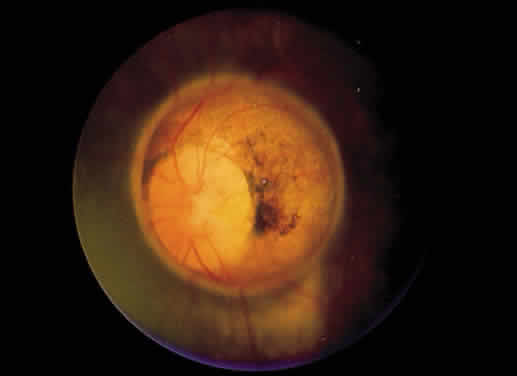

Retinochoroidal colobomas are glistening white or yellow defects with distinct borders that occur inferior or inferonasal to the optic disc (Fig. 12). They may extend up to and involve the optic disc (Fig. 13), or they may be seen as isolated chorioretinal defects. The margins of the coloboma often are pigmented, and the defect is filled with abnormal retinal tissue. Anteriorly, the defect can extend as far as the iris and produce an inferonasal gap (Fig. 14). These anomalies may occur in otherwise normal persons or in association with chromosomal abnormalities or multisystem diseases, such as trisomy 13, the Aicardi syndrome, Goldenhar's syndrome, and the CHARGE association.148,152,153 Occasionally, autosomal dominant or recessive inheritance patterns are found, but often none are evident.152 In families with autosomal dominant inheritance, variable expression of the genetic trait makes genetic counseling difficult.154

Fig. 12. Isolated retinochoroidal coloboma with pigmented borders positioned inferior to the nerve head. The sclera is visible through the thinned, overlying retinal tissue.

Fig. 13. Retinochoroidal coloboma involving the optic disc and inferonasal fundus. The borders of the abnormality are nonpigmented, and the defect appears to be filled with fibroglial tissue.

Embryologically, retinochoroidal colobomas arise from failure of the embryonic fissure to close. Consequently, the inner and outer layers of the optic cup are abnormal in this region. The inner layer (sensory retina) usually is present as a membrane of undifferentiated retina that may have blood vessels going through it (see Figs. 12 and 13). The outer layer (RPE) is absent, and since the choroid is dependent on the RPE for its development, it also is lacking.